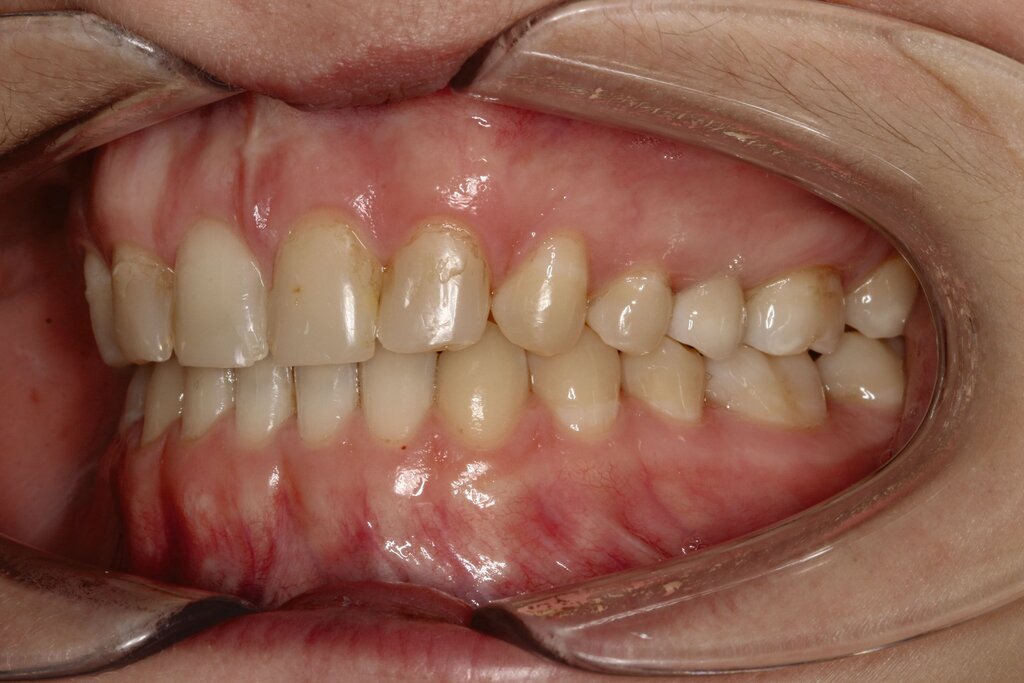

Bei dem gut zwölfjährigen Mädchen sind die seitlichen oberen Schneidezähne (Zähne 12 und 22) nicht angelegt. Zusätzlich zeigten sich verlagerte zweite obere Prämolaren.

Im vorliegenden Fall stand der Zahn 23 bereits im Mesialstand bei hoher Lachlinie und tendenziell konkavem Lippenprofil. Bezüglich Morphologie und Farbe waren die Zähne 13 und 23 nicht ausgeprägt eckzahntypisch. Es bestand kein Platzmangel im Gegenkiefer. Die Patientin war bei der Erstdiagnose 12,5 Jahre alt und im Wechselgebiss der zweiten Phase mit atypischer Durchbruchreihenfolge. Es bestand eine geringfügige Klasse II. Der Overjet war vergrößert bei vertikaler Wachstumstendenz, der Overbite war um circa einen Millimeter vergrößert aufgrund der geringfügigen Steilstellung der Oberkiefer-Front. Es bestand der Verdacht auf Nichtanlage der Weisheitszähne, 15 und 25 waren verlagert.